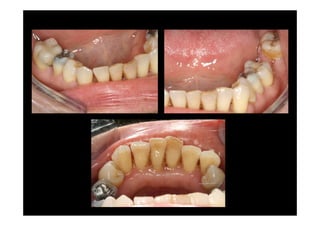

Prosthodontic rehabilitácion

SEPARION OF

INTERDENTAL

PAPILLAE

Modified papailla

preservation technique

BUCCAL DISPLACEMENT

OF INTERDENTAL

PAPIALLAE

POSTOPERATIVE

VIEW